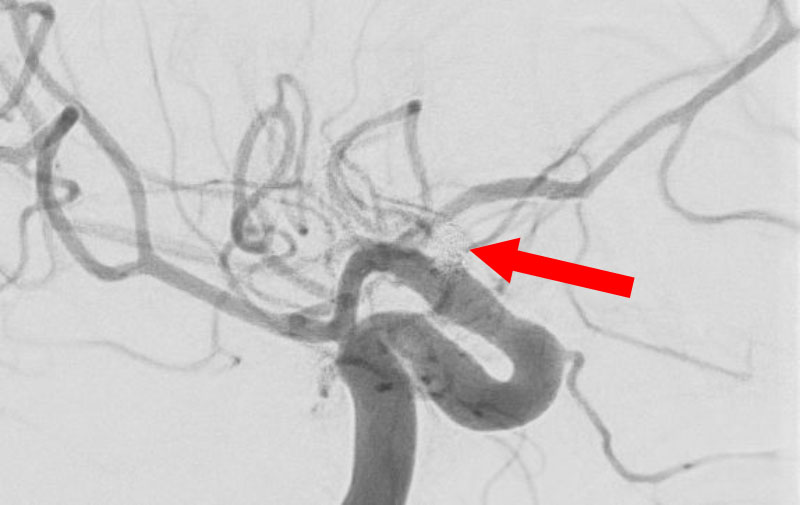

No.1593 手術前

No.1593 手術中

No.1593 手術後

'25年11月

くも膜下出血

右内頚動脈後交通動脈

分岐部動脈瘤破裂

60代

救急外来